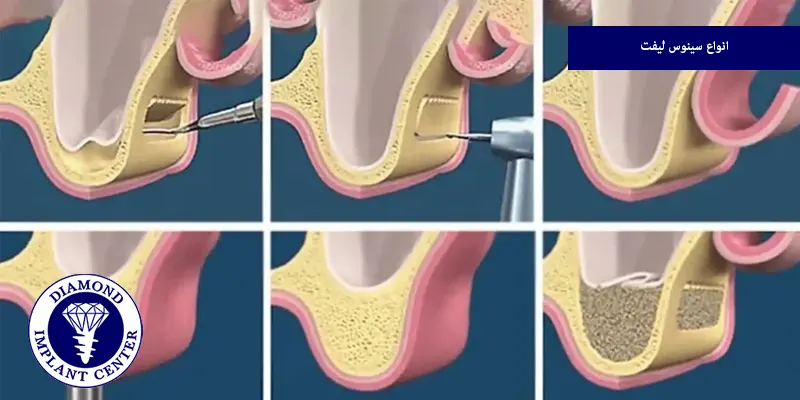

انواع سینوس لیفت

سینوس لیفت دو روش دارد که در ادامه به بررسی تفاوت سینوس لیفت باز و بسته خواهیم پرداخت.

سینوس لیفت باز

در این روش جراح با ایجاد یک برش در دیواره خارجی استخوان فک بالا به سینوس دسترسی پیدا میکند و پس از بالا بردن غشای سینوس، مواد پیوند استخوانی در محل قرار میگیرند و این روش در مواردی با کاهش شدید استخوان انجام میشود.

سینوس لیفت بسته

دندانپزشک ابتدا یک سوراخ برای نصب ایمپلنت ایجاد میکند و سپس با استفاده از ابزارهای جراحی خاص، مواد استخوانی را به فضای خالی وارد میکند، گاهی اوقات میتوان با استفاده از روش لیفت سینوس بسته، ایمپلنت را در همان روز نصب کرد، برای بیمارانی با کاهش خفیف تا متوسط ارتفاع استخوان مناسب است و زمان بهبودی کوتاهتری دارد.